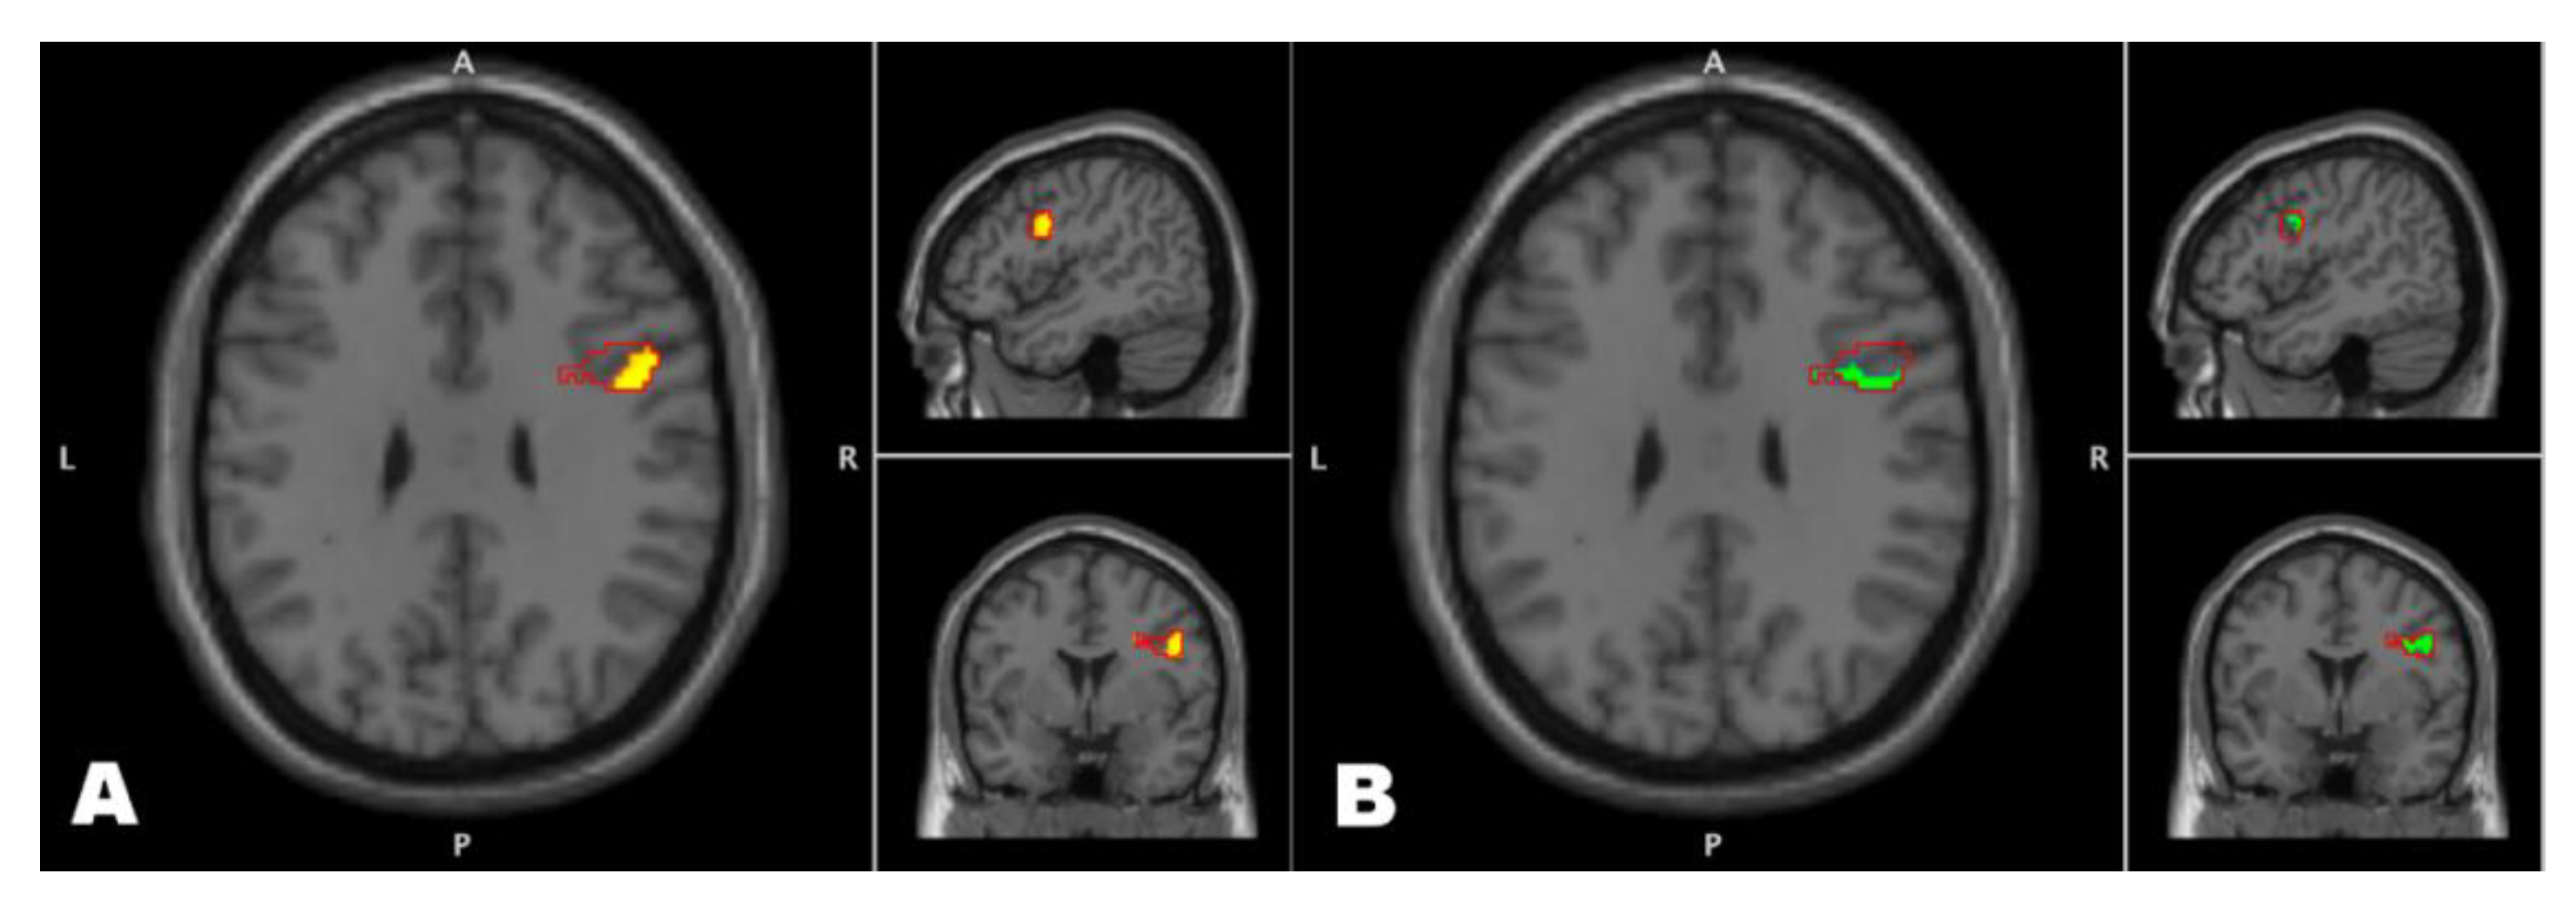

3.2. Seed-Target Tests of between and within-Group Effects

3.3. Exploration of Functional Connectivity ROI to Whole Brain